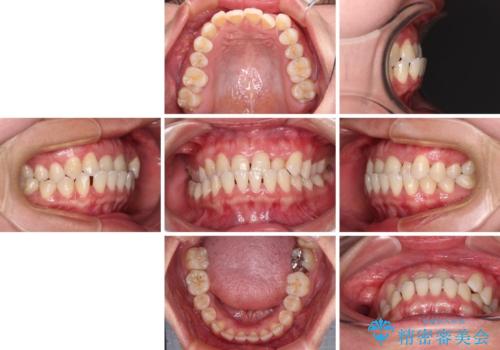

上顎の拡大に伴い反対咬合があっという間に改善されました。

元々の歯列不整は軽微であったため、僅か1年の期間で治療を終えることができました。